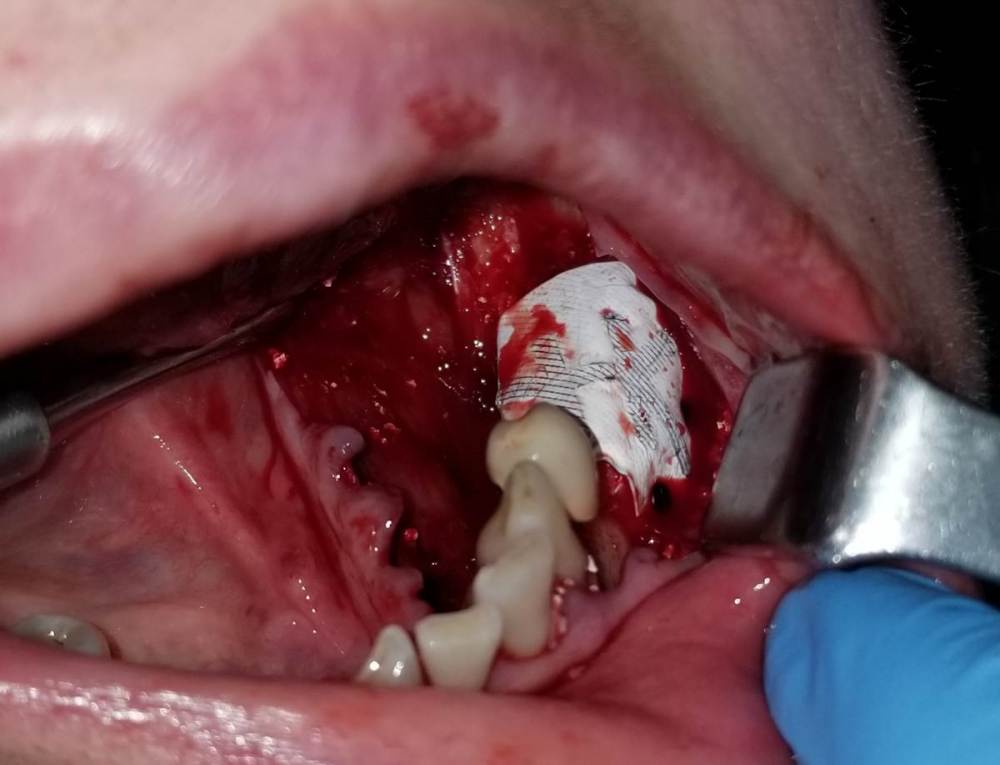

Kostoprav Опубликовано 11 мая, 2021 Поделиться Опубликовано 11 мая, 2021 (изменено) 70%ауто+30% ксено, мембрана цитофлекс, винты самосверлящие после пластики до установки имплантов прошло 8 мес. Изменено 11 мая, 2021 пользователем Kostoprav 3 6 Ссылка на комментарий

Карен Аванесов Опубликовано 12 мая, 2021 Поделиться Опубликовано 12 мая, 2021 20 часов назад, Kostoprav сказал: 70%ауто+30% ксено, мембрана цитофлекс, винты самосверлящие после пластики до установки имплантов прошло 8 мес. Замечательно! 1 Ссылка на комментарий